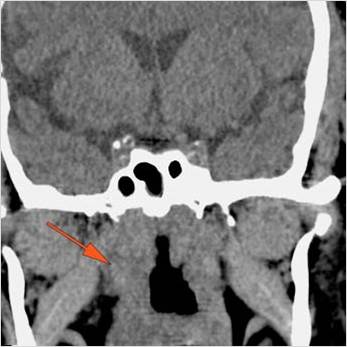

There is evidence of thrombus, thrombophlebitis or other occlusive or inflammatory process of the cavernous sinus. [Yes/No]

There is evidence of inflammation of the distal internal carotid artery. [Yes/No]